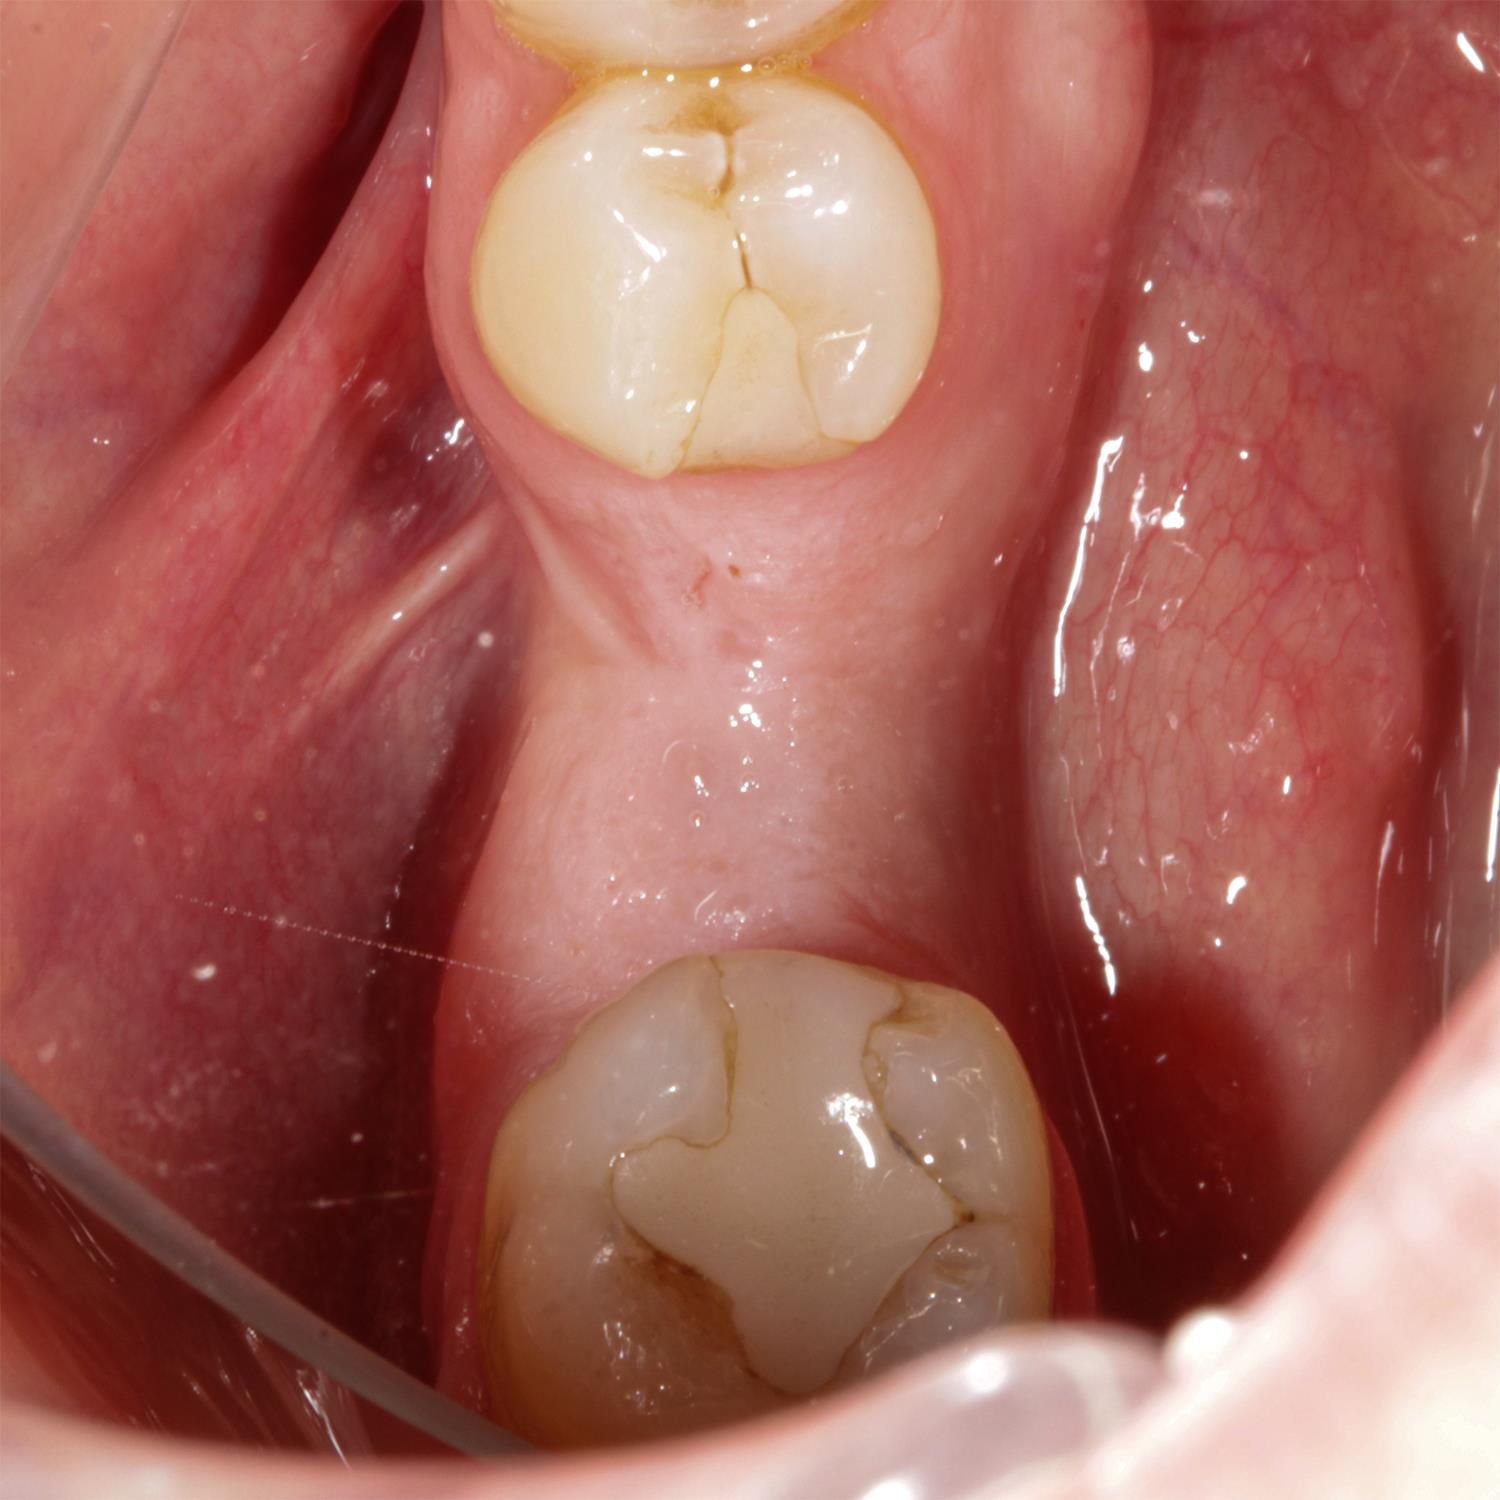

Kemik tozu ve PRF ile sert ve yumuşak doku ogmentasyonu yapıldı.